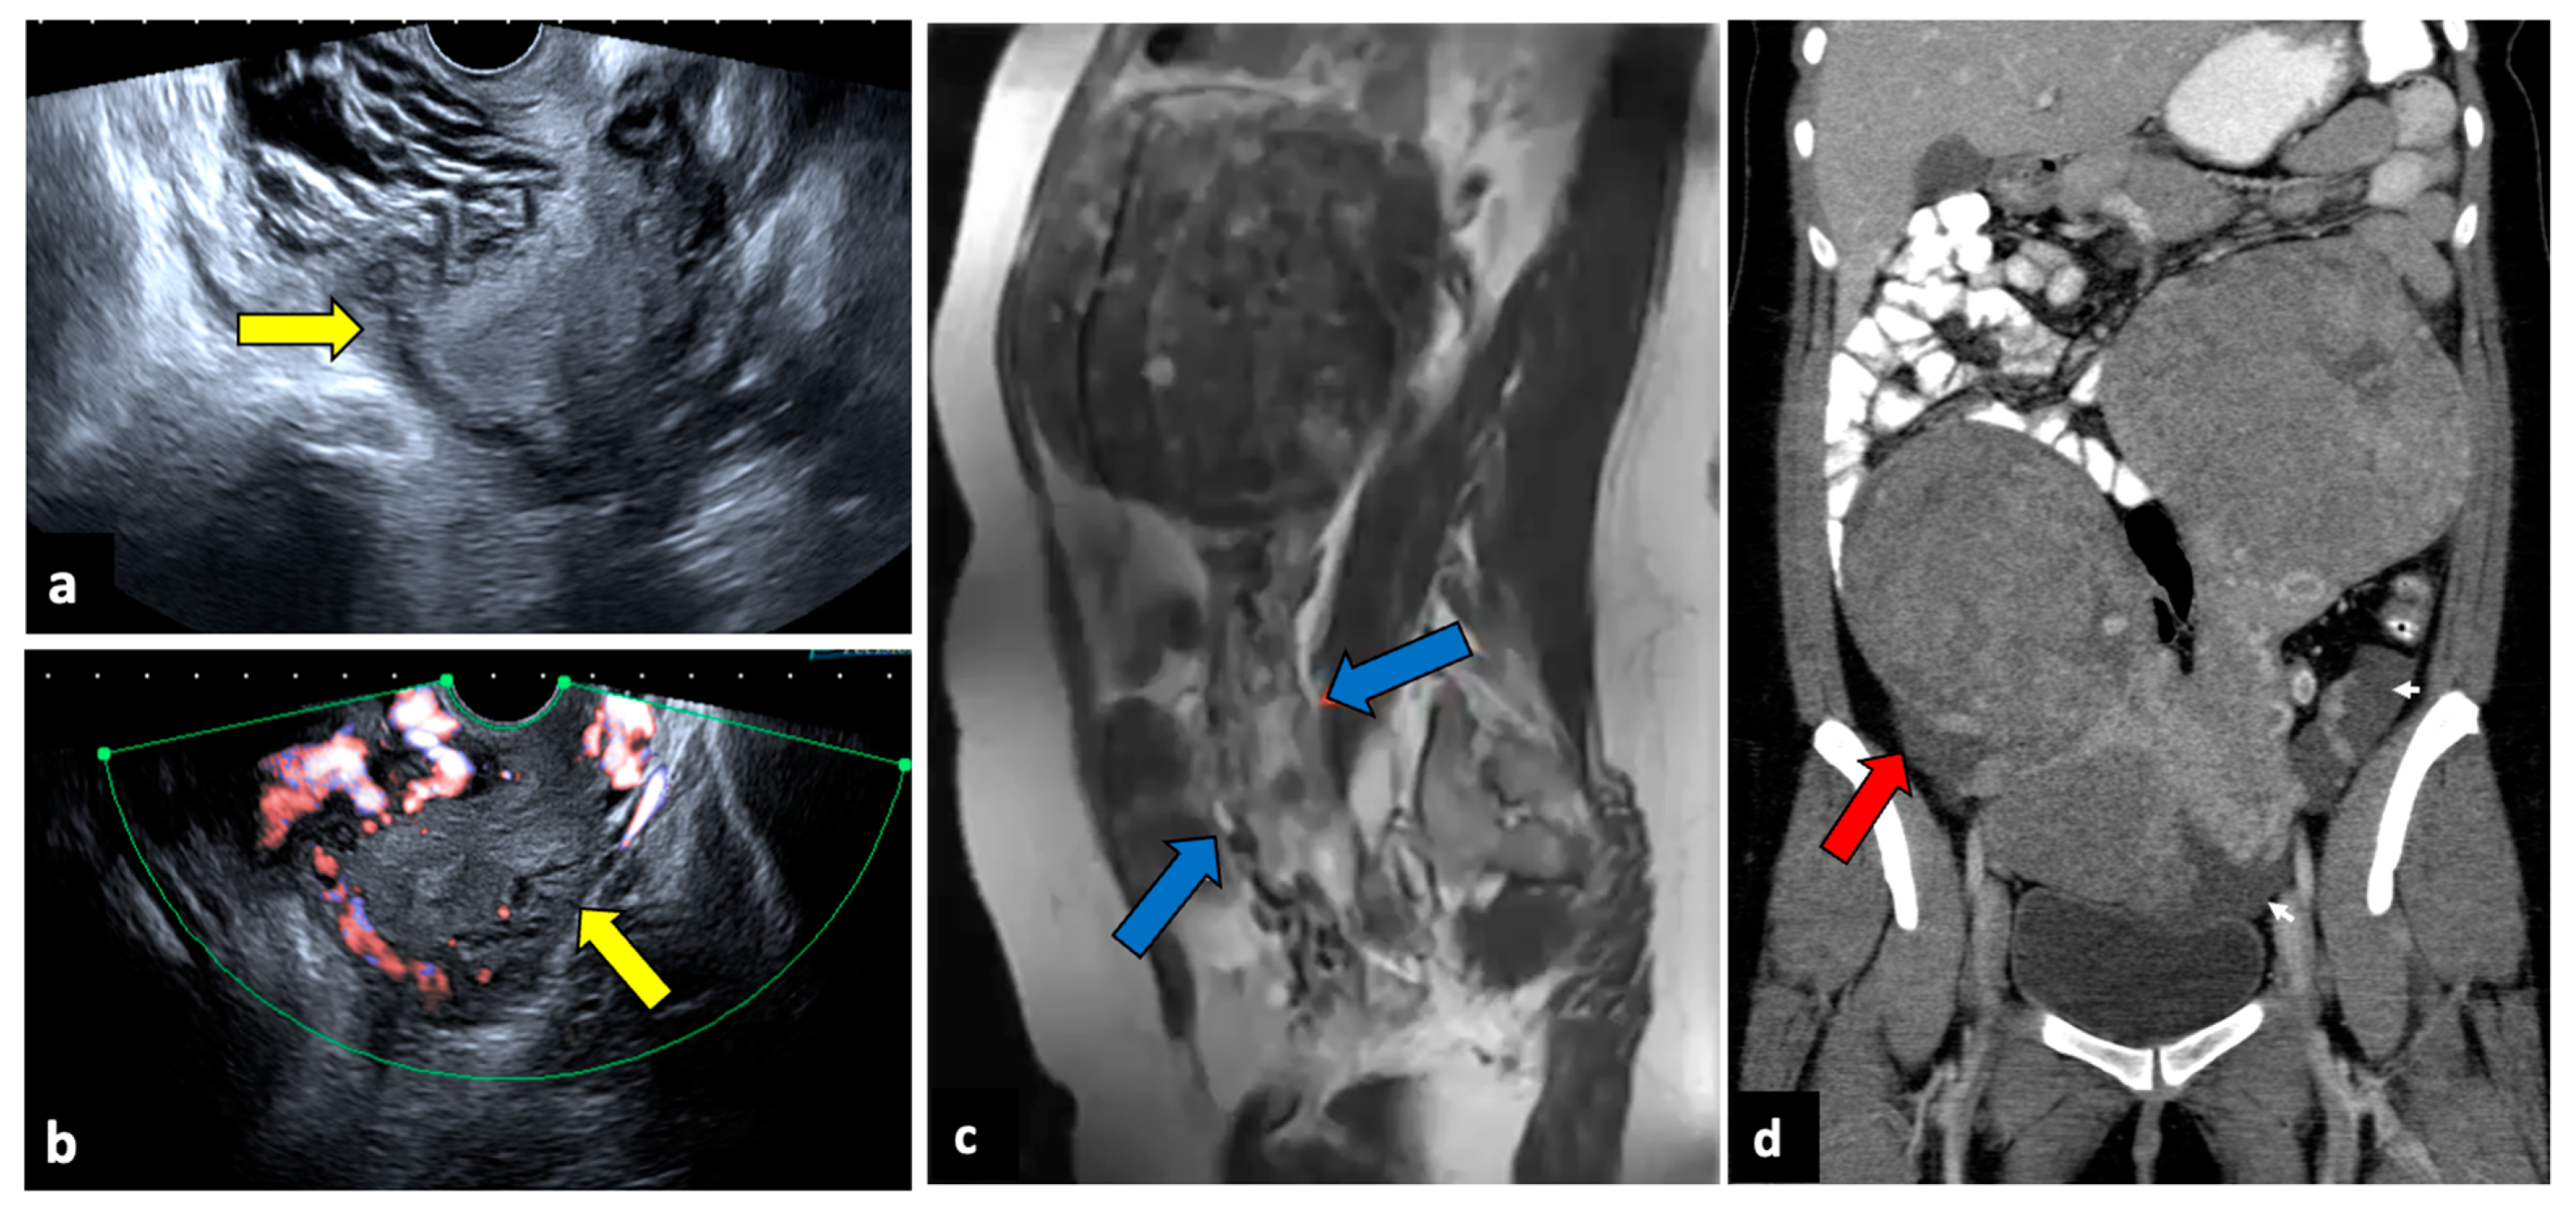

2.6. Complicated Ovarian Teratomas

2.9. Ectopic Pregnancy